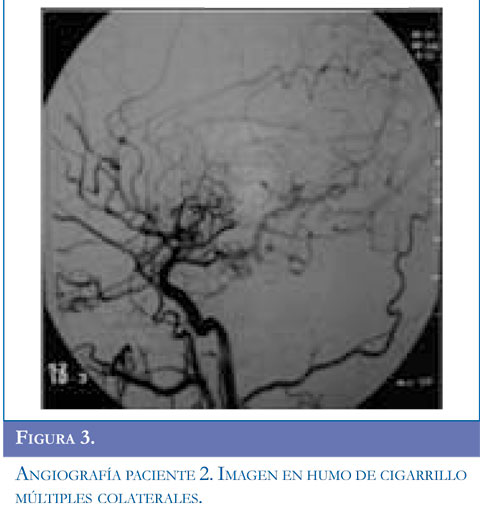

Ingresa al servicio de urgencias por presentar alteración de la marcha dado por disminución de la fuerza en hemicuerpo derecho y dificultad para el habla, acompañado de movimientos clónicos de miembro superior derecho, sin perdida de conciencia la mirada de 10 segundos de duración, se repiten en 5 oportunidades y ceden con benzodiacepinas. Se inició manejo anticonvulsivante. Al examen tenía parálisis facial derecha periférica, hemiparesia derecha con hiperreflexia músculotendinosa, disimetría, disdiadococinesia ipsilateral y afasia motora. Se realizó TAC simple de cráneo y contrastado con lesión gangliobasal izquierda de características isquémicas. Presentó clonias de brazo y aumento de la debilidad faciobraquial derecha, hemianopsia heterónima derecha, se realizó RMC con hipodensidad parieto temporal izquierda compatible con lesión isquémica en territorios de arteria cerebral media izquierda. Se inició enoxaparina1mg/k/dosis y calcio antagonista. El perfil hematológico fue normal. La panangiogra-fía evidenció enfermedad de Moyamoya estadio V de Suzuki. Valorado por neurocirugía se consideró manejo quirúrgico y el día 19 del cuadro clínico se realizó encefaloduroarteriosinangiosis. En la actualidad tiene afasia motora en mejoría, hemiparesia derecha y componente distónico ipsilateral, hiperre-flexia derecha, continúa manejo con fisiatría, terapia física, ocupacional y del lenguaje. Figuras 1,2 y 3.

La enfermedad de Moyamoya es un desorden infrecuente, de etiología desconocida, caracterizado por oclusión progresiva de la porción terminal de la arteria carótida interna y porción proximal de las arterias cerebrales medias y anteriores (1). En 1969, Suzuki y Takaku utilizaron el término Moyamoya, expresión Japonesa que significa “bocanada de humo de cigarrillo flotando en el aire”; para describir y definir esta enfermedad según los hallazgos angiográficos (2).